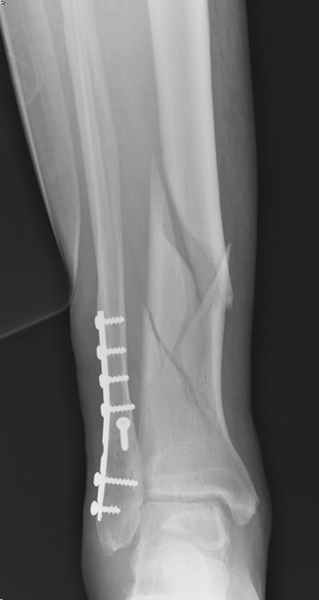

Перелом голени

спрашивает что делать с больным который поступил недавно, фермер 55 лет падение при пьяной драке в баре, года два назад перенес операцию на лодыжке, на снимках и КТ перелом без вовлечения сустава,

какие будут рекомендации? Djoldas Kuldjanov, MD Department of Orthopedic Surgery St. Louis University Medical Center